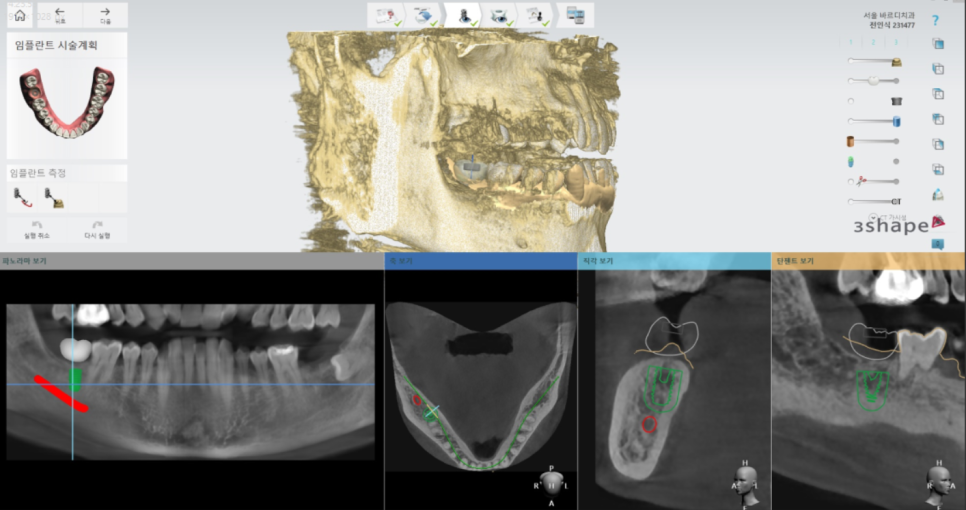

고덕동 임플란트 수술을 준비하기위해

자 이제 고덕동 임플란트 수술을 위해

제가 준비하는 부분!!

3D-CT를 통해 해부학적 구조물과 뼈를 파악하고

환자분의 구강 상태를 분석하는데

어떤 위치에 고덕동 임플란트를 심으면 좋을지

시뮬레이션을 돌려보고 또 돌려봅니다.

1-2년 쓰실것이 아니기 때문에

최적의 위치를 생각하는거죠~

임플란트 사이즈와 길이도

미리 정해두고요!

찍어놓은 구강 내 사진도 보고

X-RAY도 돌려보고 하면서

보고 또 봅니다.

그리고 나서 모델을 만듭니다.

제 방에 작업 기계가 있어서

직접 만듭니다.

중간에 뻥 뚫린 구멍은

원하는 위치에 정확히 심기 위해 가이드 해주는 구멍입니다.

단단한 뼈에 구멍을 뚫어

고덕동 임플란트 수술을 하다보니

조금만 삐끗해도 잘못된 각도로 심어질 수 있습니다.

실수없이 원하는 각도에 심기위한

보조 장치다 생각하시면됩니다.

네비게이션 임플란트 기술을 이용하여

최적의 위치를 파악했으니

그대로 심어야겠죠??